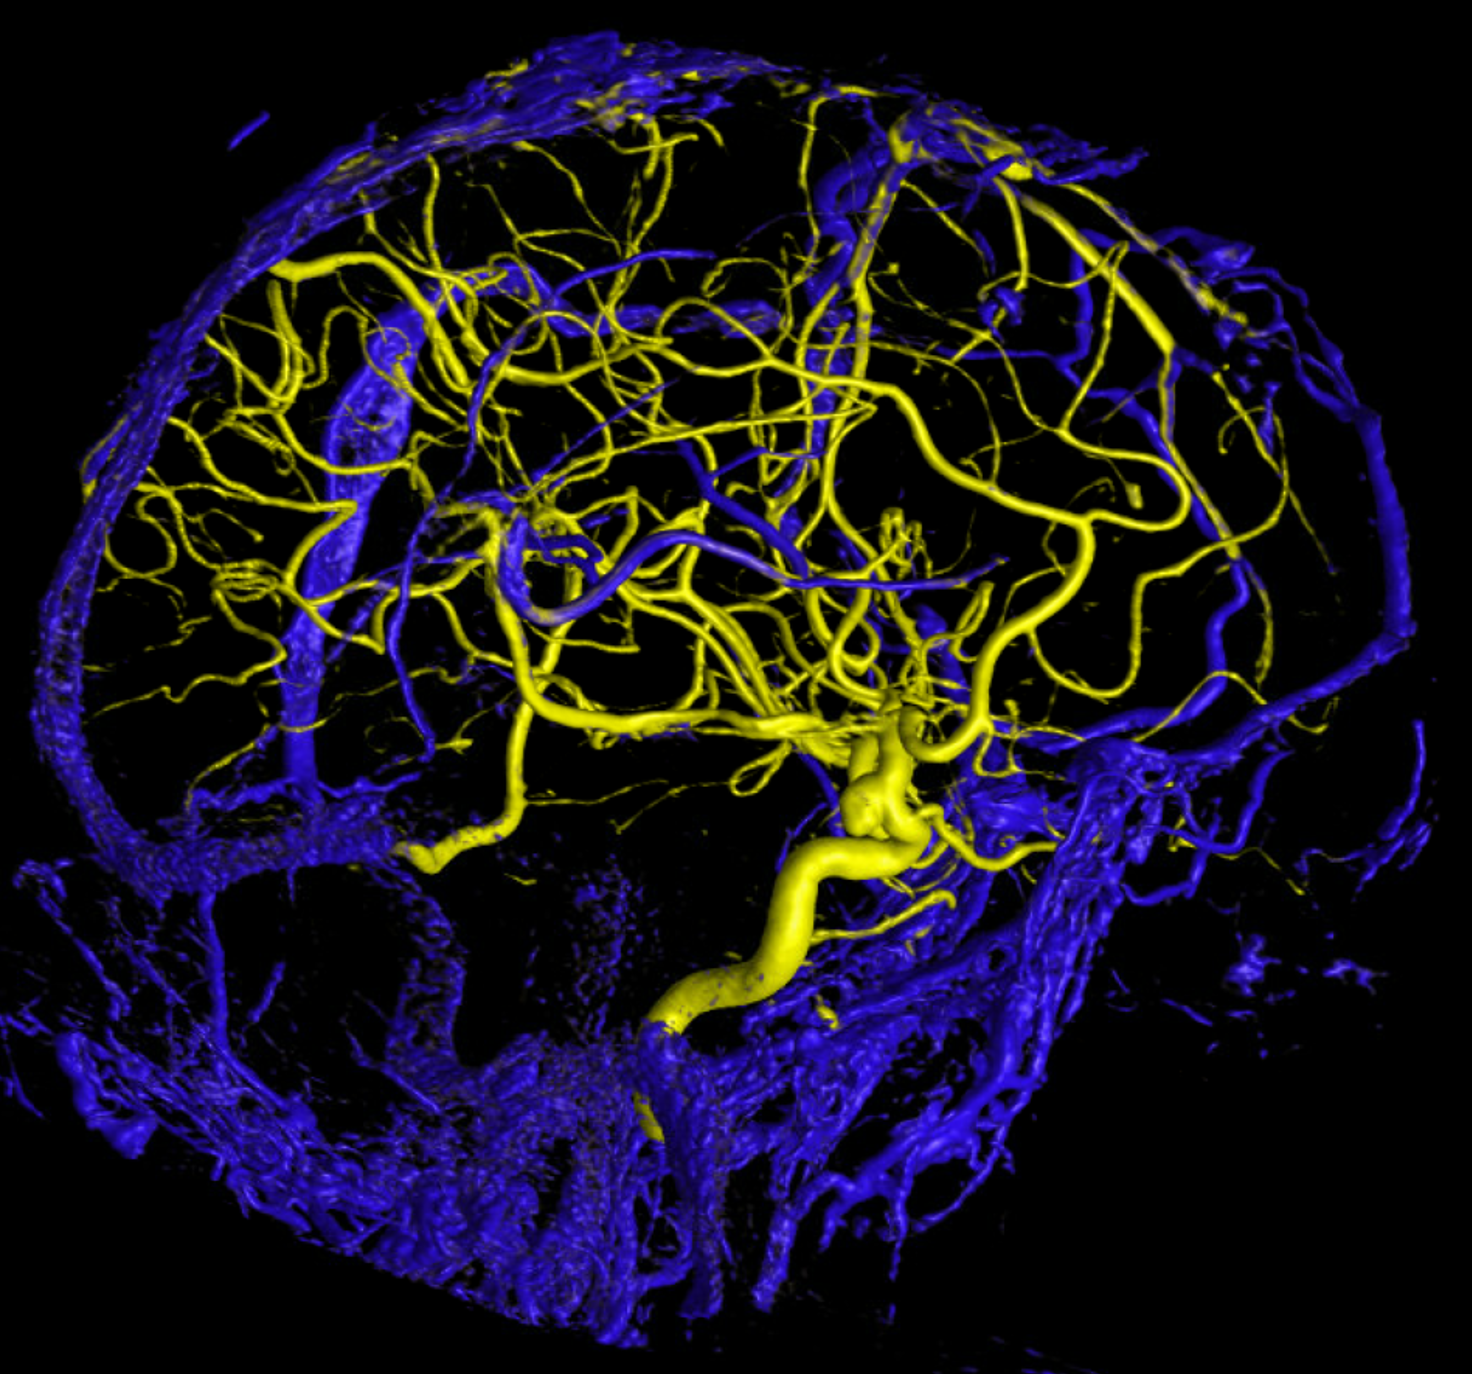

Below are some volumetric images, before we dive in

Pause movies to scroll thru individual frames